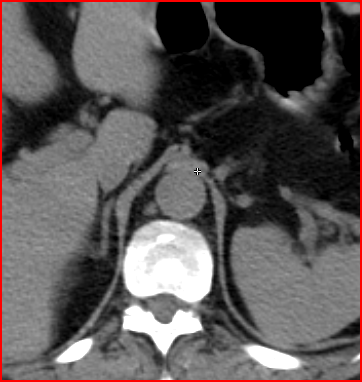

The greatest precision of image registration is achievable if the patient experiences minimal motion differences (the patient lies in the same position and imaging takes place almost at the same time) during both examinations. These requirements are met in hybrid imaging methods, with the implementation of the so called hardware registration. PET-CT, SPECT-CT or the newly emerging PET-MR examinations are all able to utilize hardware registration. The integrated PET/SPECT-CT method represents the latest technical developments of both PET and CT scanners, combined in one machine. It is capable to represent structural and metabolic information simultaneously and identically. The machine’s PET/SPECT and CT components are aligned along the common axial axis, and as the patient table moves along their longitudinal axis, the two examinations are carried out only minutes apart from each other, minimizing any movement or change in the patient’s position. During evaluation the identical slices of CT and PET can be matched with each other and they can be analyzed independently or represented in a fusion image. (Figure 1.)

1. Fusion images; FDG PET-CT, transversal and coronal planes. The dominance of certain components (transparency) can be constantly adjusted on the fused image.